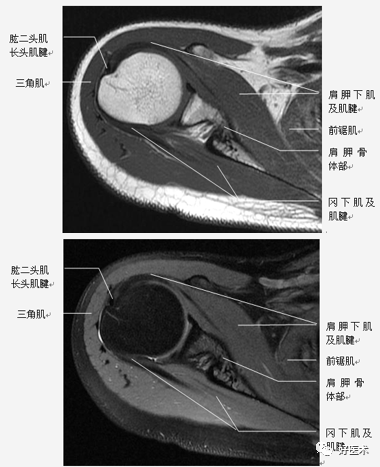

肩关节固有肌群

(2)肩袖

肩袖是由冈上肌、冈下肌、小圆肌和肩胛下肌的肌腱构成。前三个肌腱由上向下均止于肱骨大结节,而肩胛下肌腱止于肱骨小结节。